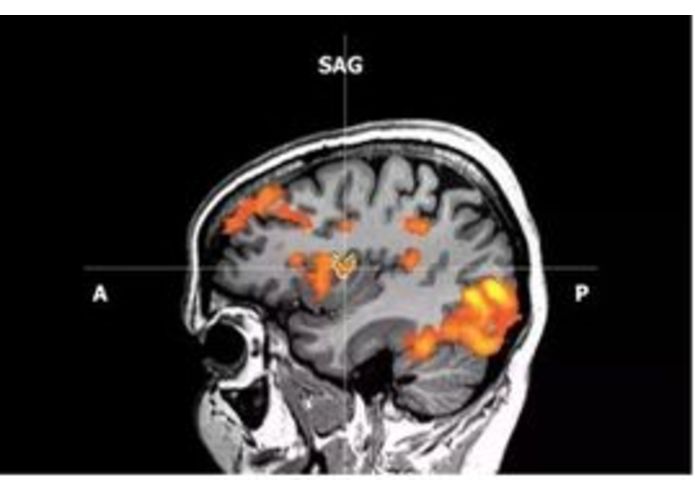

What I learned: “The brain is designed to make you survive. It’s 2 million years old. It doesn’t have a saber-toothed tiger to worry about so it worries about how do I look, what do people think of me, so we make up this stuff to suffer about inside our head cause the mind is saying flight or fight but you’re more than your mind.” ..”You bring someone into the lab. They say they are feeling fear. You scan them with an mri you can see that their amygdala response is heightened, you can measure the sweat on their palms and see that there is a galvonic skin response. You can check their blood cortisol and see that it is spiking, see these now are considered objective third person measures of fear but if half of the people came into the lab and showed none of these signs when their cortisol spike, these objective measures would no longer be objective measures of fear.”